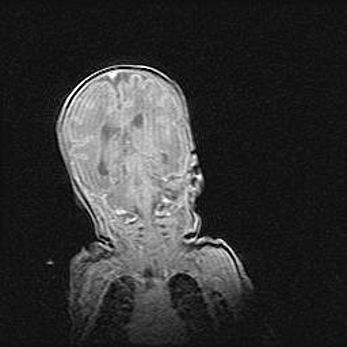

Неполная лизэнцефалия (пахигирия). Открытая гидроцефалия.

Возраст: 17 дней

Вес: 3110 г

Пол: мужской

Окружность головы: 33,5 см

Срок гестации: 35-36 недель

Лизэнцефалия—недоразвитие корковой пластинки и мозговых извилин в результате нарушения миграции нейронов коры. Поверхность мозговых полушарий гладкая. Микроскопически выявляется отсутствие нормальных слоев коры и скопление групп нейронов в подкорковом белом веществе.

Пахигирия—уменьшение числа вторичных извилин. В пораженном полушарии нервные клетки образуют толстый недифференцированный слой с неправильно расположенными нервными волокнами и группами гетеротопных клеток. Нервные клетки незрелые. Белое вещество истончено. При этом нередко аномально развит корково-спинномозговой путь.